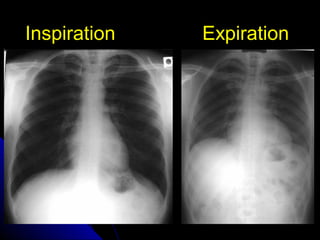

DDeeggrreeee ooff iinnssppiirraattiioonn

TThhee lleevveell ooff iinnssppiirraattiioonn ccaann bbee eessttiimmaatteedd

bbyy ccoouunnttiinngg rriibbss.. VViissuuaalliizzaattiioonn ooff nniinnee

ppoosstteerriioorr rriibbss,, oorr sseevveenn aanntteerriioorr rriibbss oonn aann

uupprriigghhtt PPAA rraaddiiooggrraapphh pprroojjeeccttiinngg aabboovvee

tthhee ddiiaapphhrraaggmm wwoouulldd iinnddiiccaattee aa

ssaattiissffaaccttoorryy iinnssppiirraattiioonn..

IInnssppiirraattiioonn EExxppiirraattiioonn

DDeeggrreeee ooff iinnssppiirraattiioonn TThhee lleevveell ooff iinnssppiirraattiioonn ccaann bbee eessttiimmaatteedd bbyy ccoouunnttiinngg rriibbss.. VViissuuaalliizzaattiioonn ooff nniinnee ppoosstteerriioorr rriibbss,, oorr sseevveenn aanntteerriioorr rriibbss oonn aann uupprriigghhtt PPAA rraaddiiooggrraapphh pprroojjeeccttiinngg aabboovvee tthhee ddiiaapphhrraaggmm wwoouulldd iinnddiiccaattee aa ssaattiissffaaccttoorryy iinnssppiirraattiioonn.. 10